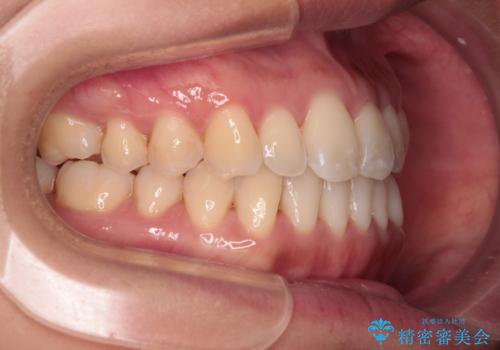

- 前歯のデコボコで前方に出ていることを気にして来院された患者様です。

上顎前歯が捻れて前方に飛び出しており、下顎前歯もそれに沿うようにデコボコとなっていました。

IPR(歯と歯の間を削る処置)によりスペースを獲得して上下顎前歯のデコボコを改善し、飛び出している前歯が引っ込むように設定し、インビザラインにて矯正治療を行うこととしました。

装着時間を守ってくださったので、予定通りの期間で終えることができました。インビザライン特有の、奥歯の咬み合わせの問題もなく、しっかりと歯列を改善することができました。